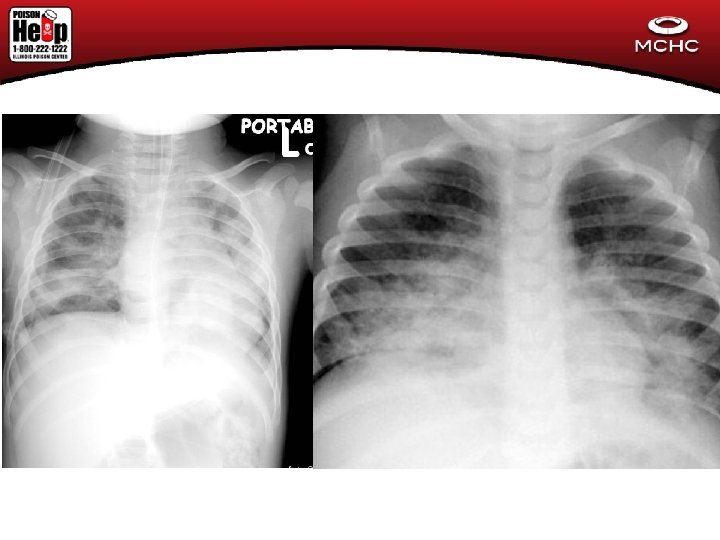

Hydrocarbons • Important signs and diagnostic exam results – Mental status – Respiratory status • Cough • Tachypnea • Grunting/Flaring/Retractions • Fever • Pulse ox • CXR

Case #1 (Christmas Tox) • 18 month old child thought to have a respiratory infection (cough and vomiting) by family comes to ED for evaluaton. • CXR shows FB in esophagus

Button Battery # 2 • 4 yo female found pulseless and apneic with blood around mouth and nares • Initially thought to be trauma • CXR with Foreign Body in esophagus

Button Battery Case #3 • 4 yo cough for over a week. May have been treated with acetaminophen. • CXR showed a 20 mm disc in esophagus